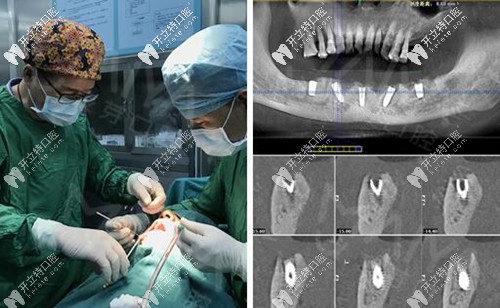

麥芽口腔的種植牙博士看過(guò)我的片子后,說(shuō)我的下半口牙槽骨萎縮厲害,現(xiàn)存的骨量不適合做傳統(tǒng)的滿口種植牙手術(shù),因此給我設(shè)計(jì)了“all-on-4”種牙技術(shù)的升級(jí)版本“all-on-5”,也就是說(shuō)恢復(fù)半口牙齒需要種5顆植體,安裝上“架橋式”的牙冠就可以了。

其實(shí),做種植牙根本沒(méi)有自己想象的疼,打完麻藥不到5分鐘就起作用了,半口種植牙的5顆牙釘不到一個(gè)小時(shí)就種完了,感覺(jué)自己就瞇了一會(huì)就好了。牙釘種好之后,戴的是臨時(shí)牙冠,不過(guò)當(dāng)天就能吃東西~~